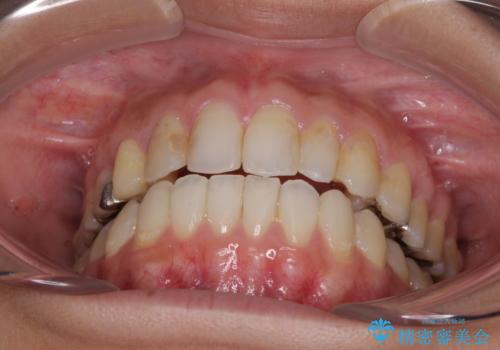

後戻りを治したい 骨格的なズレの大きい方のインビザライン矯正

- 中学生の時に矯正治療をしたものの、後戻りを気にして来院された患者様です。

骨格的に下顎が右側に変位しているため、左右の咬み合わせを理想的なものに改善することはできませんが、インビザラインにて歯列を整えることとしました。

骨格的なズレによる左右差は改善できませんでしたが、上下の正中を極力合わせるようにすることができました。